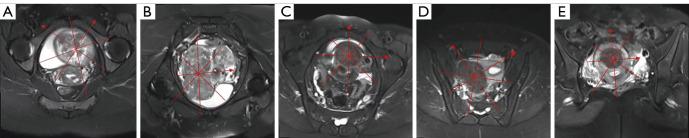

A retrospective cross-sectional study was conducted, involving imaging data from 194 patients diagnosed and treated with HIFU ablation for uterine fibroids at our institution. Patients were divided into the seromuscular-layer injury group and the intact group based on the presence or absence of perfusion defects on postoperative sagittal or axial enhanced T1-weighted imaging (T1WI) magnetic resonance images. Clinical and imaging traits potentially linked to seromuscular-layer injury were gathered and evaluated across the two groups.

The intact group comprised 139 cases, whereas the injury group comprised 55 cases. Logistic regression analysis revealed that subserous myoma (P=0.008), age ≤43.5 years (P=0.008), the thickness of the rectus abdominis muscle ≤8.06 mm (P=0.001), the energy efficiency factor ≤3.6 J/mm (P=0.002), the non-perfused volume ratio ≥67% (P=0.032), and the number of quadrants of peripheral muscle layer ≤1 (P=0.015) were the most significant influencing factors for seromuscular-layer injury in patients with uterine fibroids after HIFU treatment.